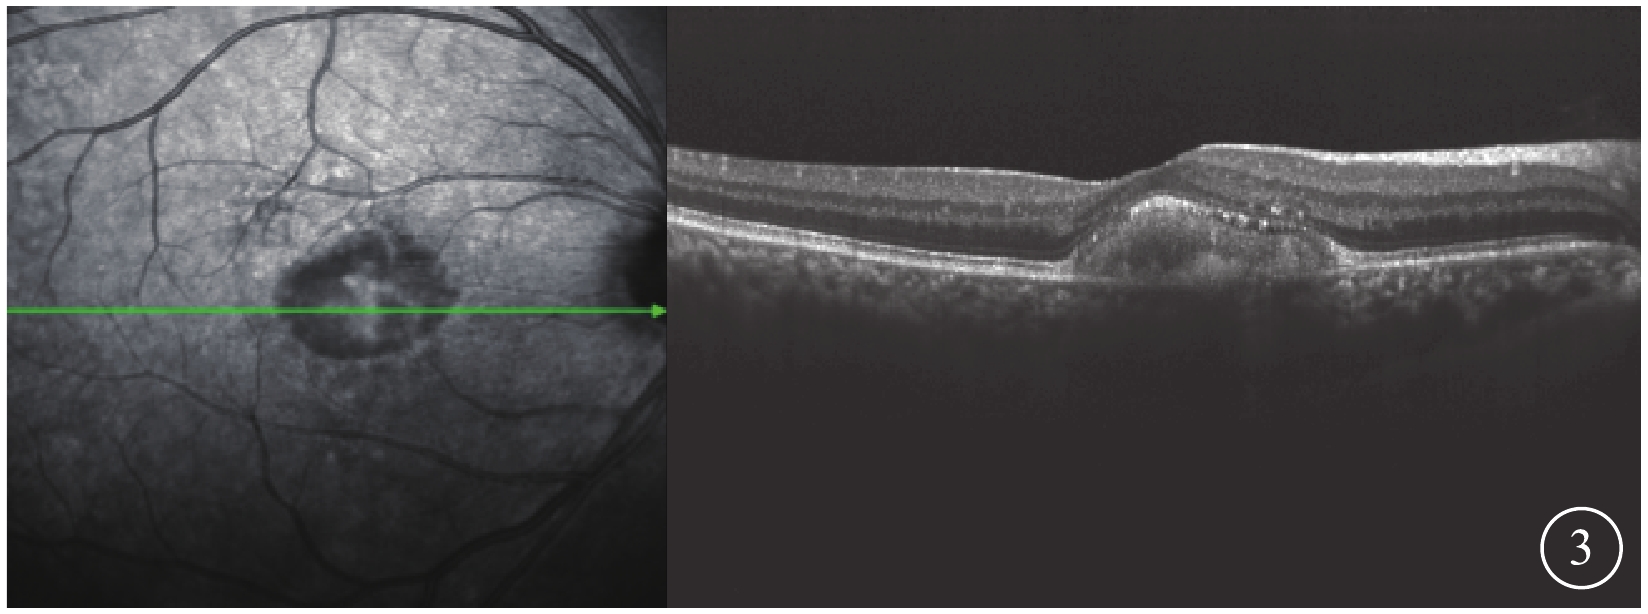

OCT檢查發現,所有患眼黃斑中心凹視網膜色素上皮(RPE)層之上可見“圓頂屋”樣隆起病灶。病灶局部的RPE層增厚,密度不均;視網膜神經上皮層除被病灶抬高外,未見明顯破裂分層現象(圖3),層間也無水腫、滲出改變。

圖3

AOFVD患眼OCT像。黃斑中心凹RPE層之上“圓頂屋”樣隆起病灶,視網膜神經上層除被病灶抬高外,未見明顯破裂分層現象

圖3

AOFVD患眼OCT像。黃斑中心凹RPE層之上“圓頂屋”樣隆起病灶,視網膜神經上層除被病灶抬高外,未見明顯破裂分層現象

OCT檢查發現,所有患眼黃斑中心凹視網膜色素上皮(RPE)層之上可見“圓頂屋”樣隆起病灶。病灶局部的RPE層增厚,密度不均;視網膜神經上皮層除被病灶抬高外,未見明顯破裂分層現象(圖3),層間也無水腫、滲出改變。

圖3

AOFVD患眼OCT像。黃斑中心凹RPE層之上“圓頂屋”樣隆起病灶,視網膜神經上層除被病灶抬高外,未見明顯破裂分層現象

圖3

AOFVD患眼OCT像。黃斑中心凹RPE層之上“圓頂屋”樣隆起病灶,視網膜神經上層除被病灶抬高外,未見明顯破裂分層現象